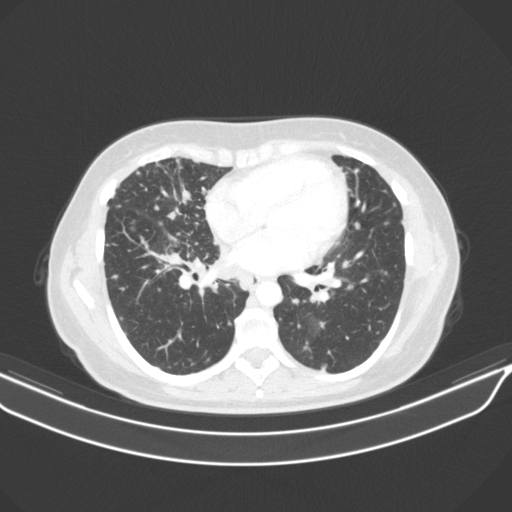

Reconstructed NATIVE CT scan (cycle consistency)

Full window (WL 1023.5, WW 4095 β†’ Low βˆ’1024, High +3071)

Lung window (WL -600, WW 1500 β†’ Low βˆ’1350, High +150)

Mediastinum window (WL 40, WW 400 β†’ Low βˆ’160, High +240)